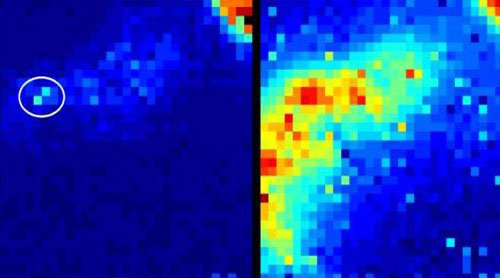

Camera mới có thể nhìn xuyên qua cơ thể.

Trong hình trên, bạn có thể thấy ví dụ về ánh sáng được máy ảnh phát hiện từ một kính hiển vi đồng tiêu được sử dụng trong phổi cừu. Hình ảnh bên trái là hình ảnh được nhìn thấy nhờ camera mới – nó tiết lộ chính xác vị trí của dụng cụ ở trong phổi. Ở bên phải, bức ảnh cho thấy khung cảnh giống như được thấy trong một chiếc máy ảnh thông thường, trong đó cảm biến bắt những tiếng động dưới dạng ánh sáng rải rác. Nhưng chúng ta không thể xác định được vị trí của các photon khi các hạt ánh sáng phát ra xung quanh cấu trúc của lá phổi.